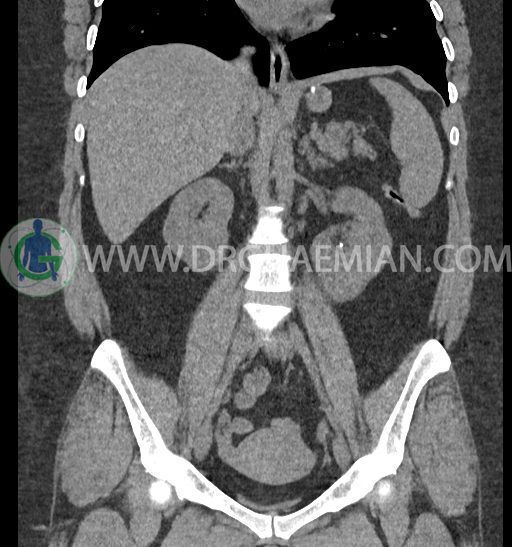

سی تی اسکن شکم و لگن با استفاده از اشعات ایکس تصاویر عرضی از ناحیه شکم و لگن ایجاد میکند. در این کیس کلیه نعل اسبی و سنگ کلیه مشاهده می شود.

در سی تی اسکن اسپیرال شکم و لگن بدون کنتراست (مولتی دیدکتور 16 با مقاطع ظریف و بازسازی های ساژیتال و کرونال) :

-horseshoe kidney

-حداقل سه سنگ 5mm در کلیه راست و یک سنگ 3mm در کلیه چپ بدون شواهدی از هیدرونفروز